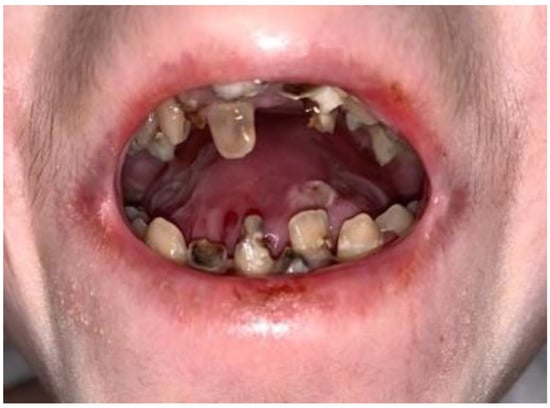

- The presence of extensive caries in individuals with DEB may result from delayed oral and dental rehabilitation due to physical disabilities, limitations and more pressing medical problems.

- Microstomy, pain from mucosal lesions, and restricted access to the mouth can be caused by poor oral hygiene.

| Tooth decay | 12 | 10 | 280 | 26 | |

| Tooth to be extracted | 0 | 0 | 141 | 26 | |

| Intraoral bulla and erosion | 1 | 1 | 23 | 26 | |

| Ankyglossia | 0 | 0 | 19 | 26 | |

| Microstomy | 0 | 0 | 18 | 26 | |